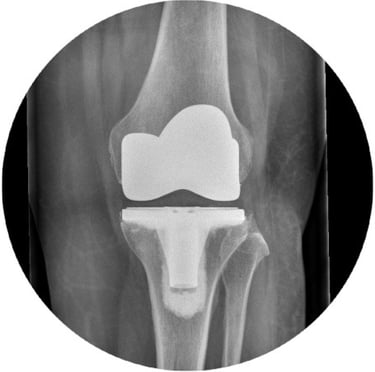

Knee Replacements:

Mr Pang performs his total knee replacements using the latest robotic assisted system to ensure optimal positioning of the prosthesis. He is also trained to perform robotic-assisted partial knee replacements.

He has experience in revision knee surgery and is adept in using megaprosthesis in more complex cases.